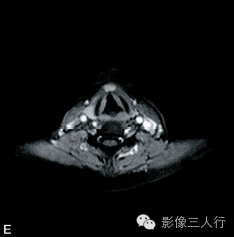

A~B. T1WI横断位;C~D. T2WI压脂横断位; E~F. T1WI压脂增强横断位;G. HE×100

卵圆形结节影位于舌骨中线,T1WI呈低信号,T2WI压脂序列呈稍高信号,信号均匀。增强后明显均匀强化,约1.3cm×0.8cm×1.6cm,其右前方下颌间隙内亦见一小结节,约0.7cm×0.4cm×0.5cm,信号特点与舌骨中线结节大致相同。颈部软组织结构清楚,未见异常信号影,气管居中,无受压或移位。颈部MRI平扫两侧见正常甲状腺组织,信号欠均匀(图A~F)。